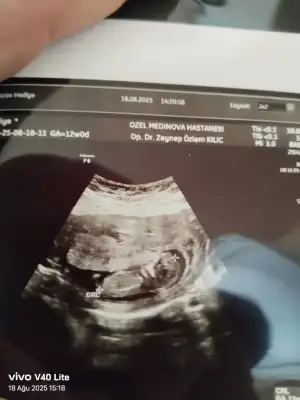

13 haftalık ultrason fotoğrafına göre cinsiyet tahmini?

Bu arkadaşımın 13+3 net değil demişler sizce erkek mi kız mı

• 501ba316-4f60-4e81-9d90-5fe7cdb88a5d.webp

501ba316-4f60-4e81-9d90-5fe7cdb88a5d.webp

27,3 KB · Görüntüleme: 91

Bakın işte burada 3 çizgi🥰 Ama henüz yeni yeni oluştuğu için yanılma payı olabiliyor tabiki😊 Gönlünüzdeki nasip olur inşallah, sağlıcakla